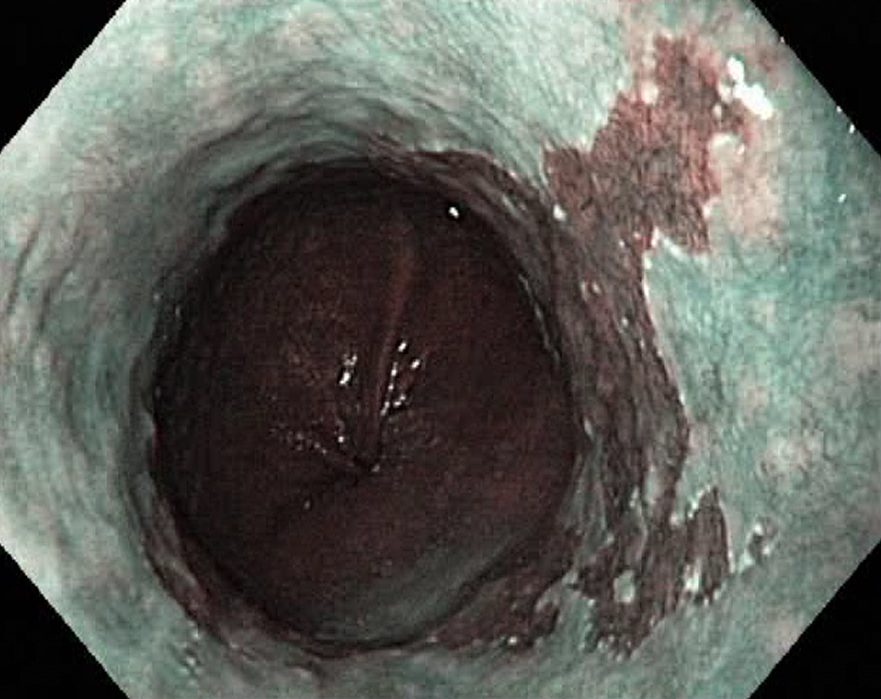

Barrets Oesophagus (NBI, Narrow Band Imaging)